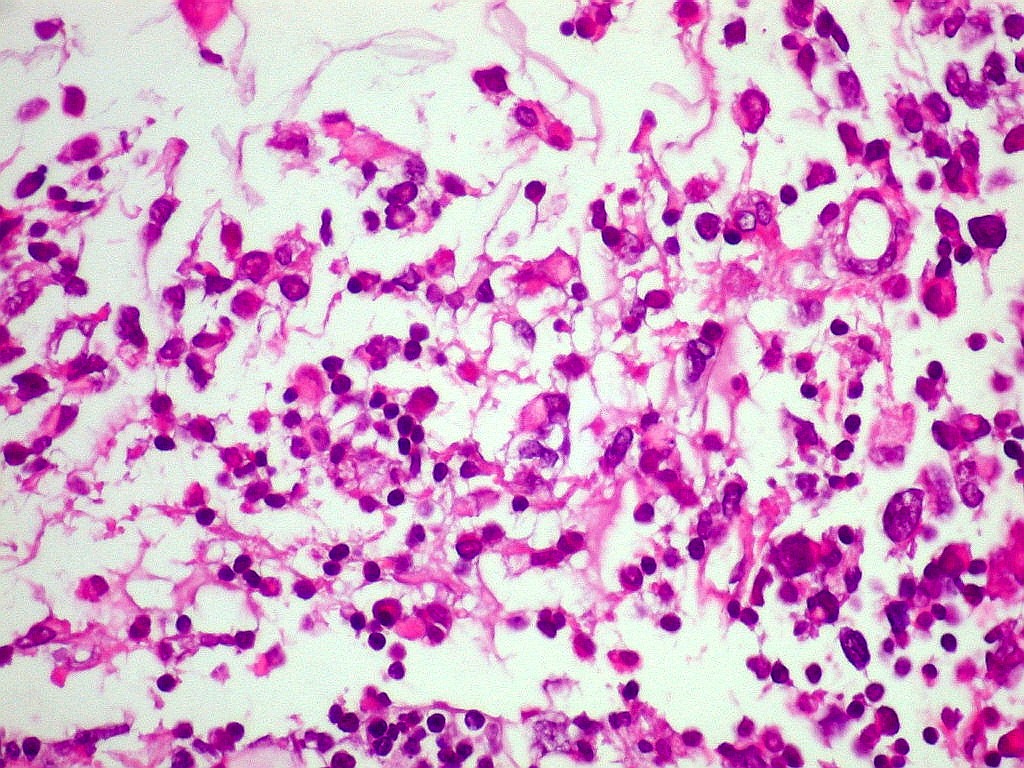

INI1.

Antígeno nuclear presente em todas as células normais.

Sua ausência é importante marcador do tumor teratóide

rabdóide atípico (metade direita do campo). Na metade

esquerda, vaso com células positivas. Os vasos não

pertencem ao tumor, mas o invadem a partir dos tecidos infiltrados. |

| INI1.

Células neoplásicas negativas (centro) e epêndima positivo

(em cima) (não neoplásico) |

Células vasculares INI1 positivas, células neoplásicas

negativas (embaixo) |

INI1. Linfócitos

positivos. Como células inflamatórias, não pertencem

ao tumor. |